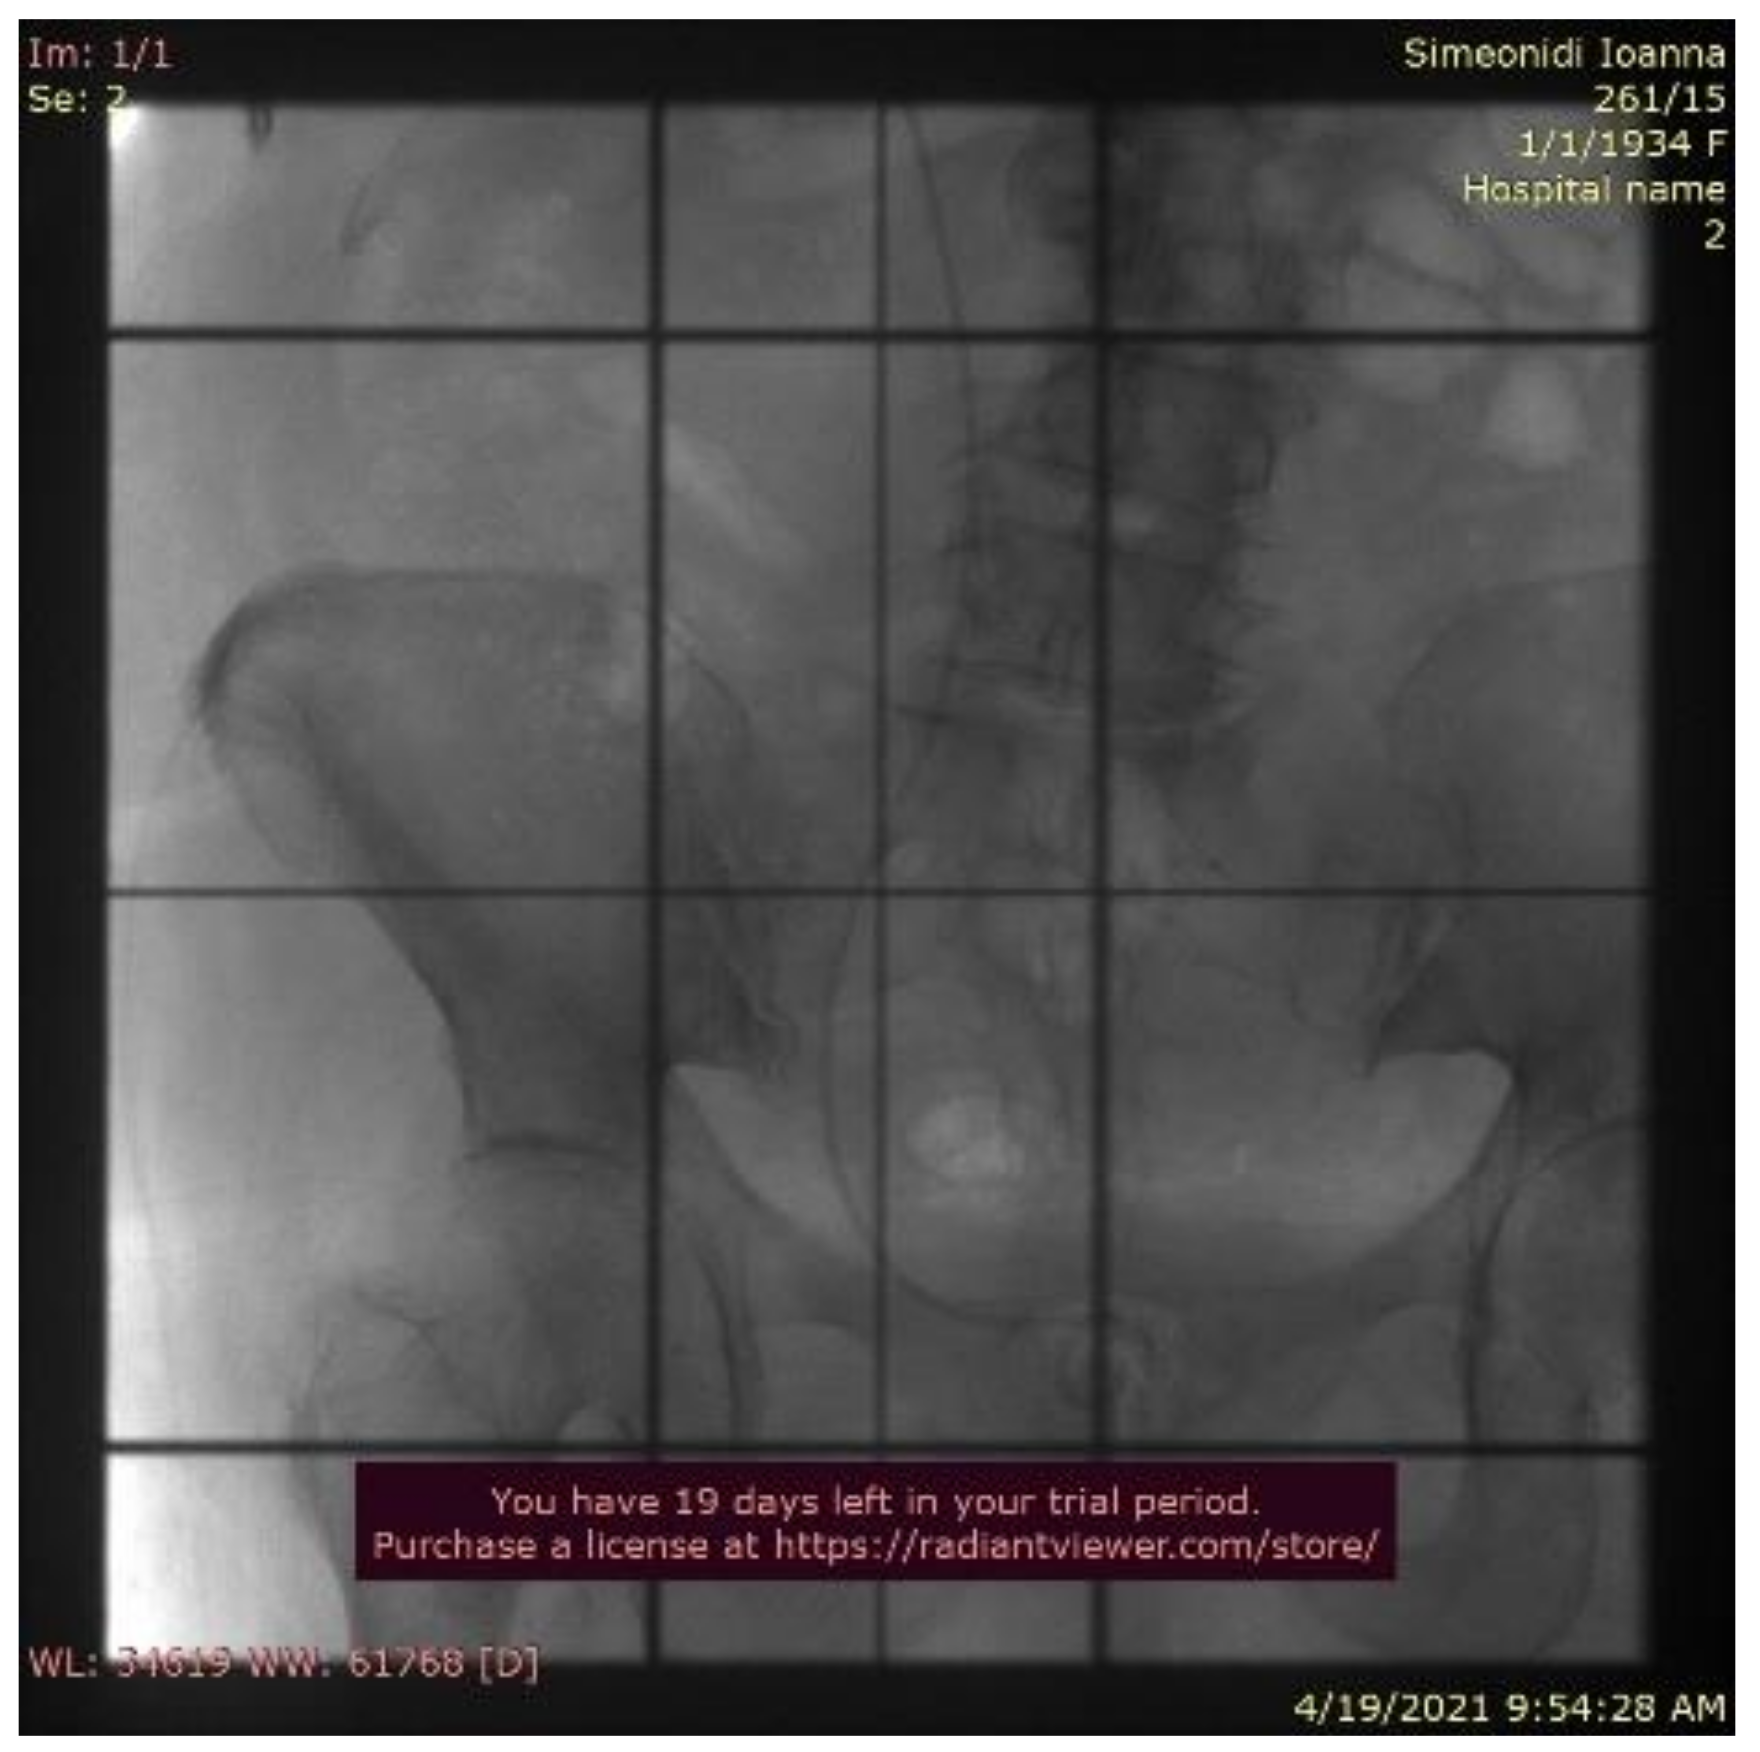

2. Case Report